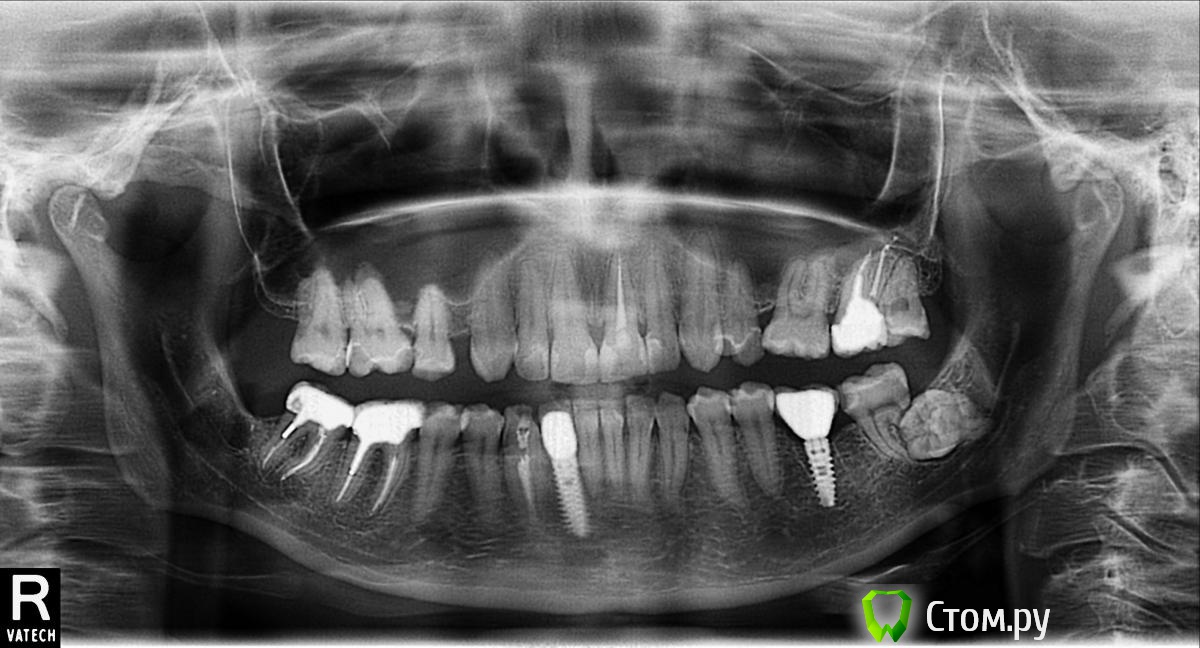

englishlady Опубликовано 17 февраля, 2014 Поделиться Опубликовано 17 февраля, 2014 Уважаемые врачи, здравствуйте.Нужна Ваша консультация. Была проведена имплантация и протезирование. Есть еще ряд проблем. Но в последнее время стал немного ныть челюсть слева, а при широком раскрытии щелкать сустав. В связи с этим вопрос: насколько необходимо ортодонтическое лечение? Или мне просто надо переделать какие-либо коронки. Просто если ситуация некритична, я бы предпочла бы этого неделать. У меня ортодонтическое лечение было уже 2 раза. В дестве была пластинка, а потом брекеты. Если можно дать какие-либо рекомендации по панорамному снимку, то я была бы очень признательна. Заранее спасибо. Ссылка на комментарий